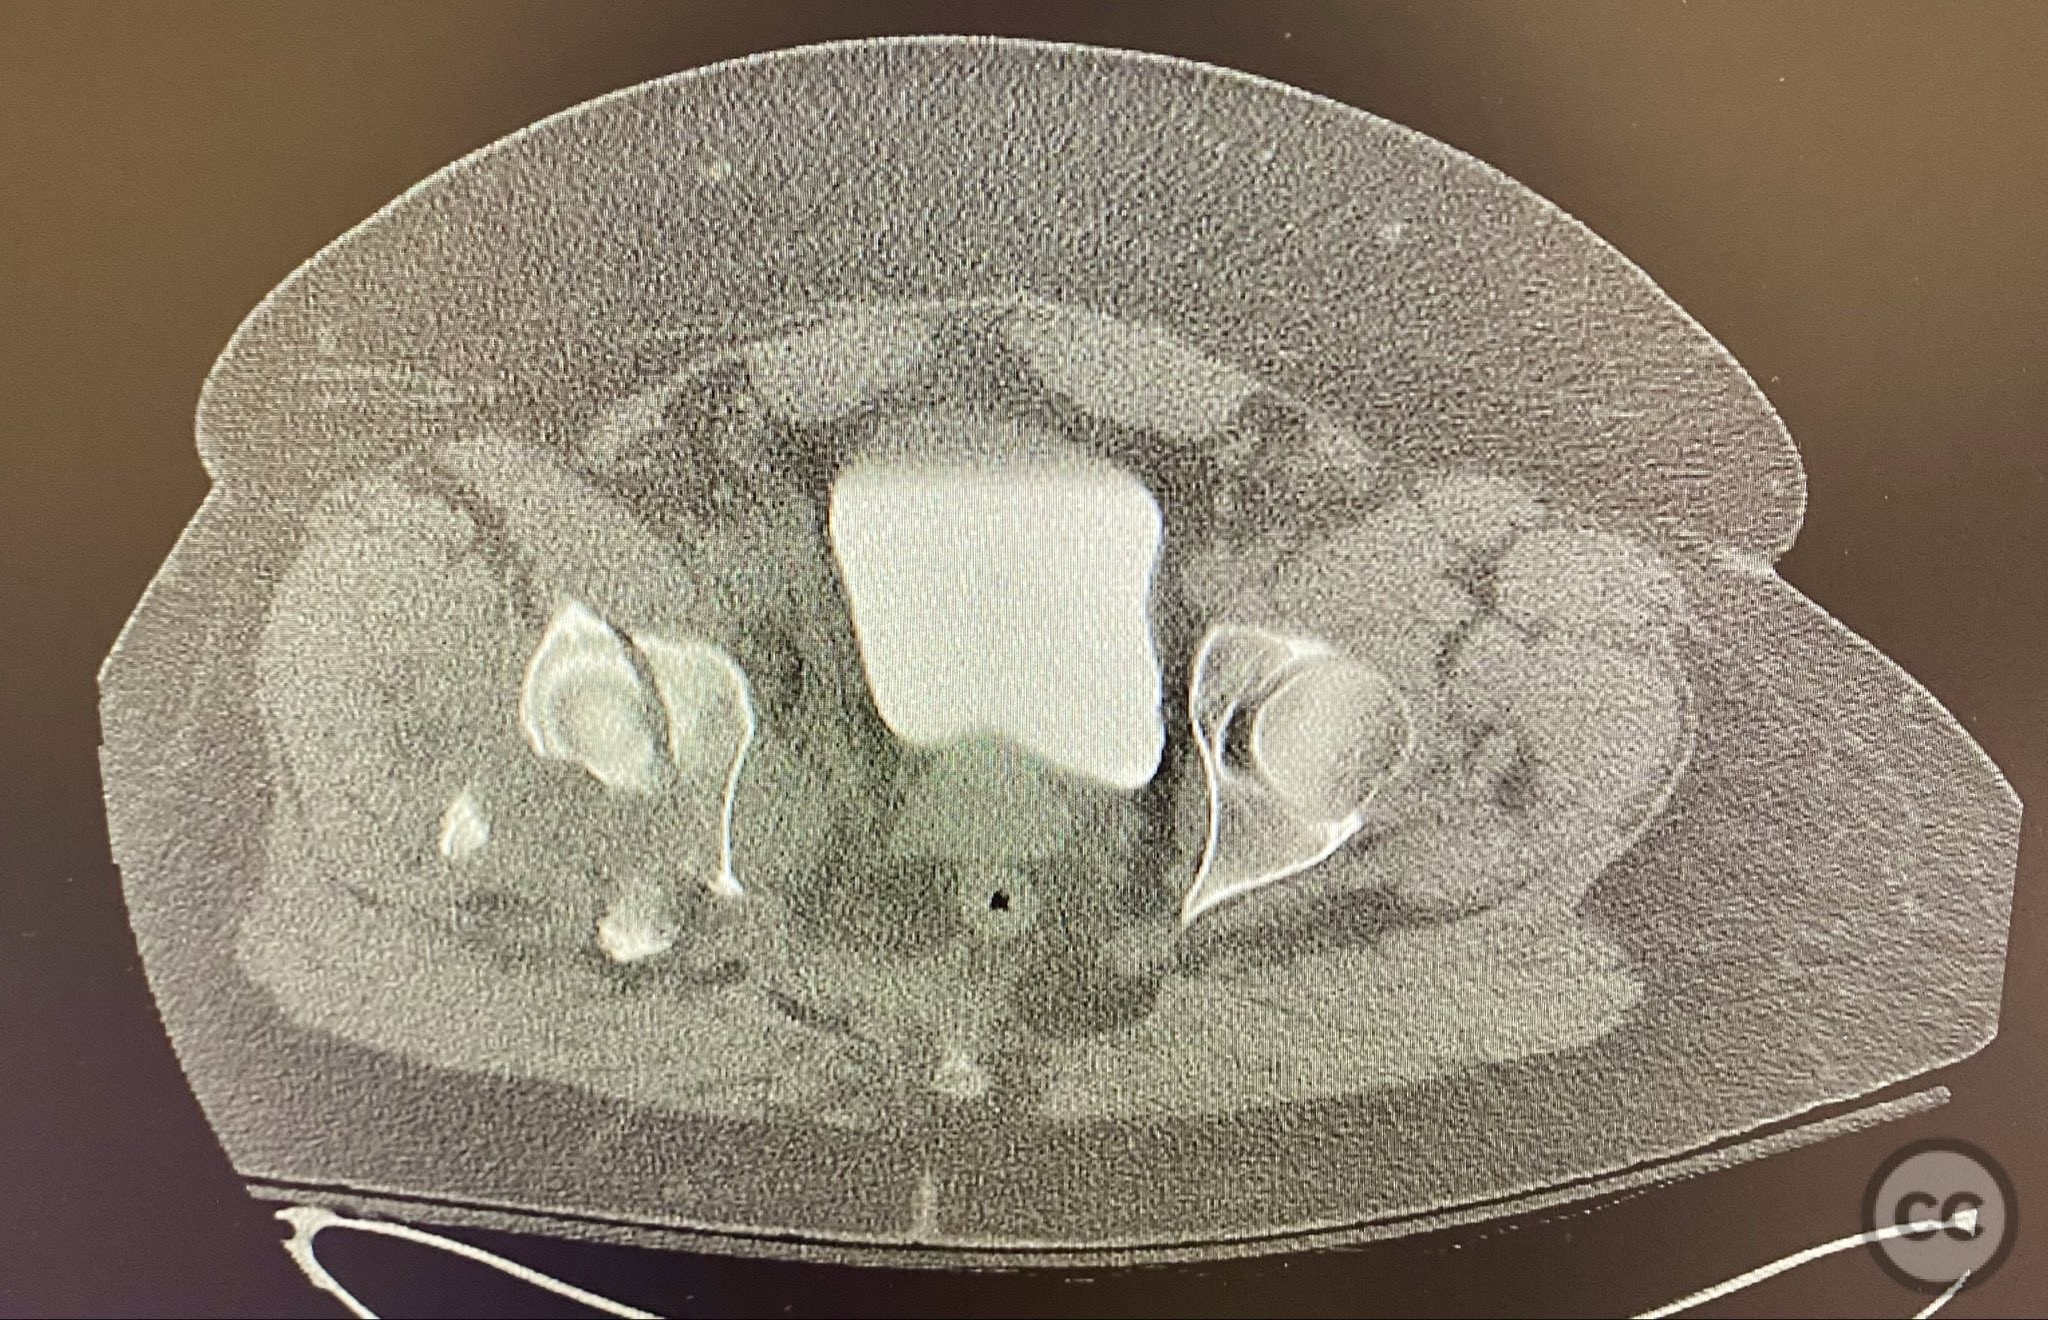

Operative remarks:

The transverse fracture was manipulated and temporarily stabilized using a reduction clamp applied across the fracture plane. Under biplanar fluoroscopic guidance, a cannulated cancellous lag screw was percutaneously inserted to achieve interfragmentary compression across the transverse component. The reduction clamp was then removed. Posterior wall fragments were anatomically reduced and stabilized with contoured buttress plates spanning both the posterior wall and providing additional stabilization to the transverse component. Postoperative CT confirmed satisfactory reduction and fixation of both acetabular columns and restoration of articular congruity.

Postoperative protocol:   Postoperatively, skeletal traction was discontinued. The patient was maintained non-weight bearing on the affected limb for 8 weeks, with early passive range of motion exercises initiated at 48 hours post-surgery. Progressive weight bearing was introduced after radiographic evidence of healing at 8–10 weeks.